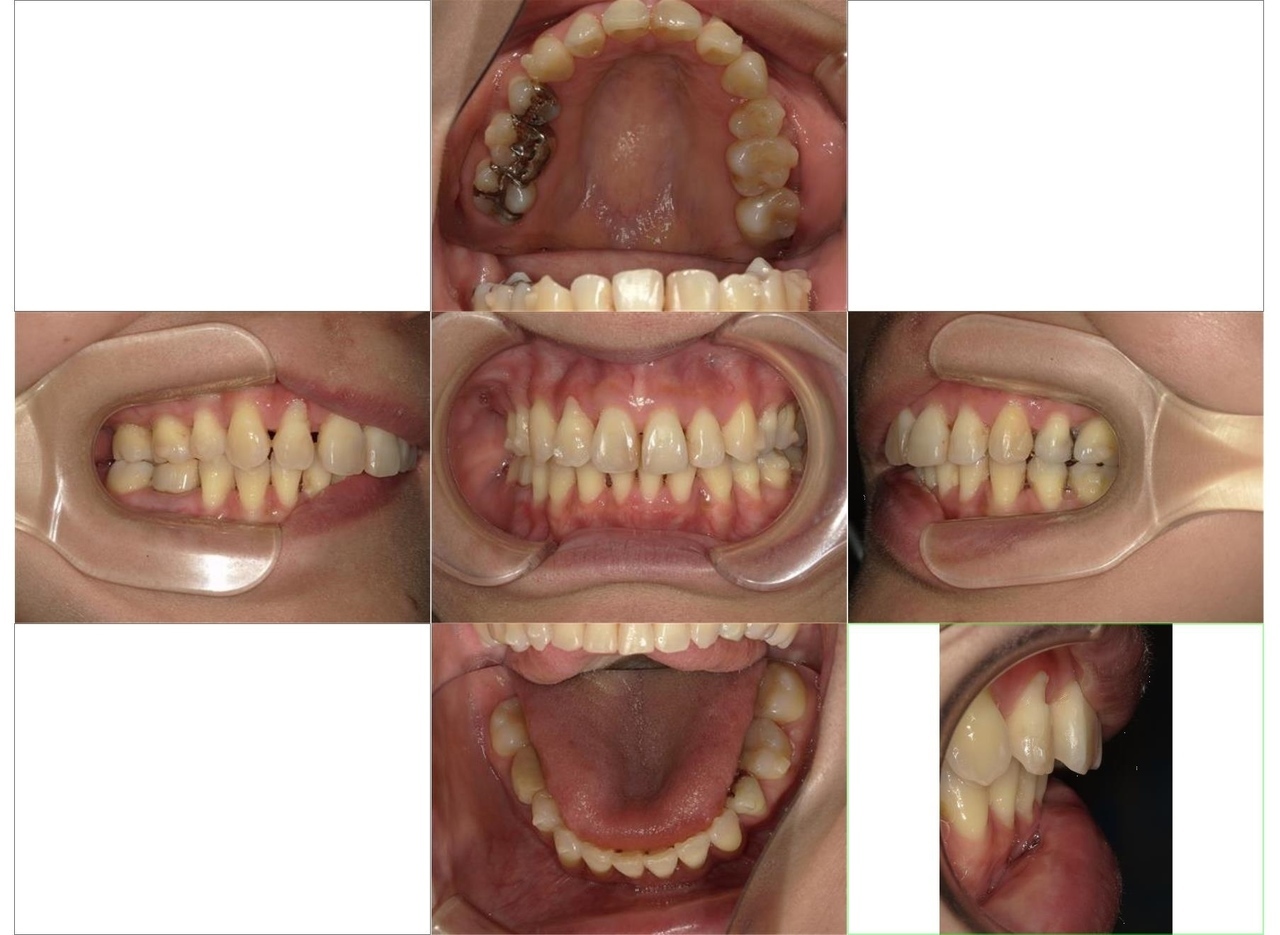

歯ならびの治療を主訴にご来院されました。上顎前歯の突出がみられ、唇が閉じにくく、麺類が食べにくいとのことでした。まず、保険診療で歯周病の治療を行いました。ワイヤー矯正とインビザラインによる矯正治療を説明し、ワイヤー矯正治療を希望されました。まず、歯を並べるためのスペースを確保するため、上顎小臼歯の抜歯を行いました。その後は、レベリング、リトラクション、正中合わせ、コントラクション、アイデアルアーチによる最終調整をしました(専門用語ですみません)術後は、食べ物が食べやすくなったこと、見た目が改善されたことを喜ばれていました。全体的に歯周病の進行が見られるため、今後は歯周病安定期治療による定期的な治療を続けていきます